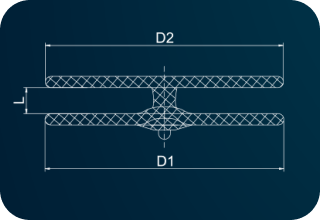

| Code | [D1]Right Disc Diameter(mm) |

[D2]Left Disc Diameter(mm) |

[L]Waist Length (mm) |

Minimum Recommended Sheath SizeSteerEase™(Fr.) |